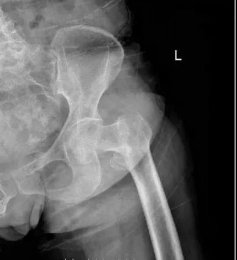

【案例分享】老年股骨轉(zhuǎn)子間骨折治療新選擇——人工髖關節(jié)置換 日期:2021-03-18 07:59:19 點擊:1922 好評:44

骨二科成功救治高齡老人右股骨轉(zhuǎn)子間骨折 濰坊市市立醫(yī)院骨二科近日為一位82歲高齡老人開展了老年股骨轉(zhuǎn)子間骨折患者的人工全髖或半髖關節(jié)置換手術(shù),取得良好的治療效果。王奶奶2月5日入院后被診斷為右股骨...

股骨粗隆間骨折是老年人常見損傷,也稱轉(zhuǎn)子間骨折,指股骨頸基底到小粗隆下平面區(qū)域內(nèi)的骨折,為關節(jié)囊外骨折。老年人骨質(zhì)疏松,肢體不靈活,當下肢突然扭轉(zhuǎn),跌倒或使大粗隆直接觸地致傷,甚易造成骨折。...